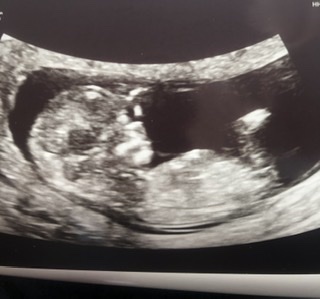

12 uker

I dag var dagen vi for første gang fikk se vårt lille barn. For forrige gang liknet det kun på en bamsemums, men i dag fikk vi se at det faktisk er en baby og ikke en fisk. Det var helt utrolig å få se en liten knøtt som sprellet og vinket til oss❤️ Mammahjerte smeltet! Nå håper jeg skuldrene kan senkes og gleden kan få bruse frem, mens jeg hviler i håpet om at det nå er vår tur til å treffe vår kjære skatt!